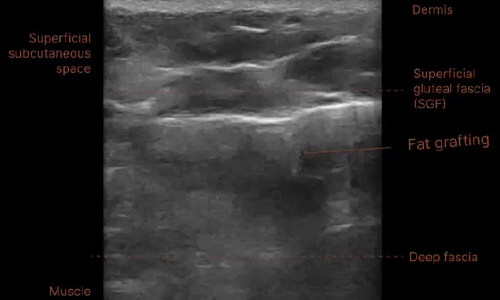

3.自體脂肪填充

超音波:

像膠原塊,亮白片塊、邊界不清。

困擾:

再天然,也怕一次打太多、太集中;養不活的脂肪就變成纖維化。

處理:

先消疤針軟化,必要時配合顯微套管微調體積。